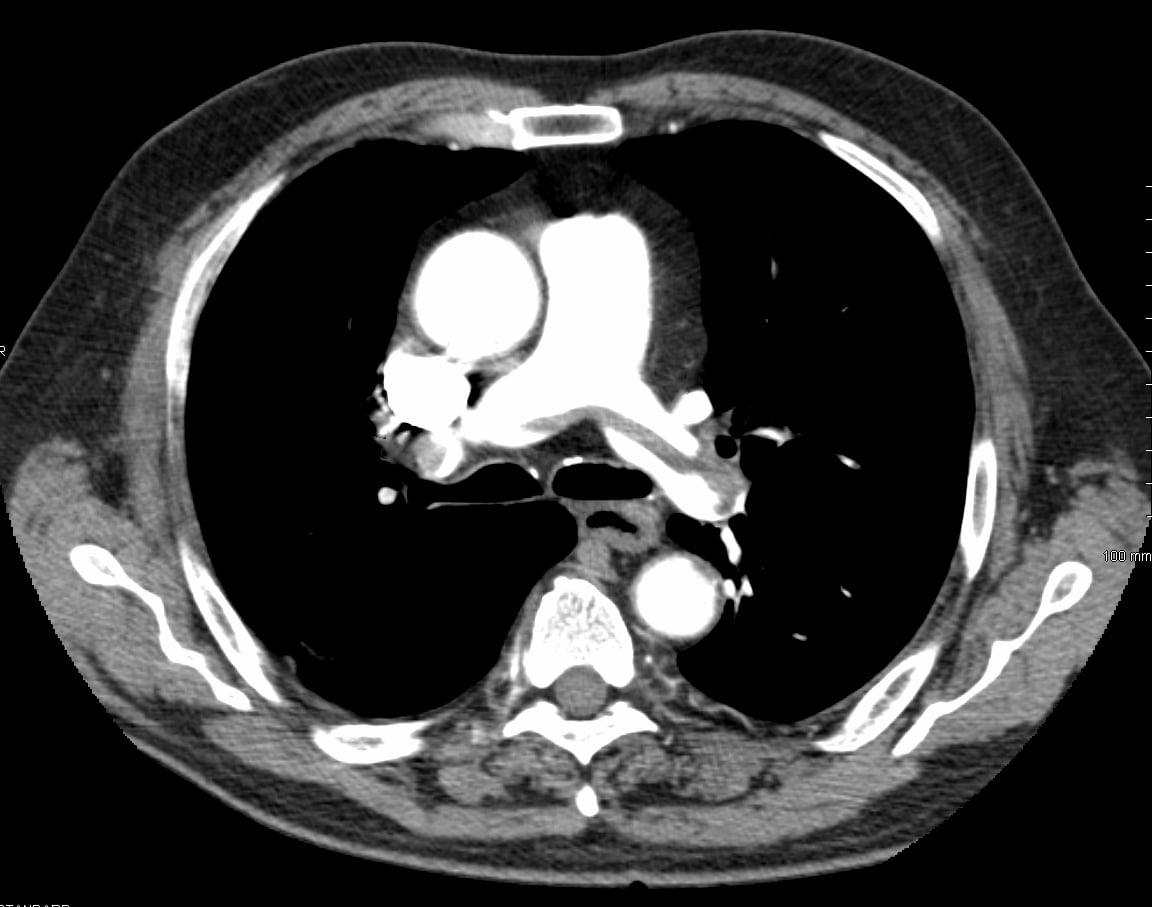

Pentru stabilirea diagnosticului se face un examen fizic al inimii, un examen radiologic, ECG, arteriografia pulmonară sau examen scientigrafic. În embolism pulmonar masiv acut, rezultatele examenului fizic vor arăta un suflu de insuficiență tricuspidiană, tahicardie, accentuarea zgomotului II pulmonar, hipotensiune arterială și distensie jugulară.

Prin examen ECG se pot depista anumite modificări la nivelul inimii și anume: o dilatare a ventriculului drept, insuficiența coronariană funcțională și ischemie. Prin investigație de radiografie pulmonară se obțin informații cu privire la severitatea embolismului.